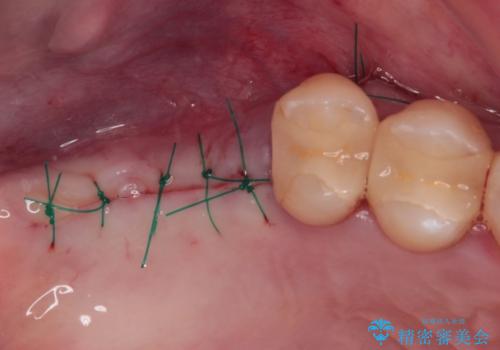

検査を行ったところ、歯周外科処置や抜歯が必要と思われる箇所が散見されたため、あらためて当院に歯周病の初期治療から行うこととしました。

多くの外科処置を行ったため、治療期間も長くなり、患者様の負担は非常に大きなものとなりましたが、明るく健康的な口元となり、患者様には大変満足していただけました。

- 外科手術のため、術後に痛みや腫れ、違和感を伴います